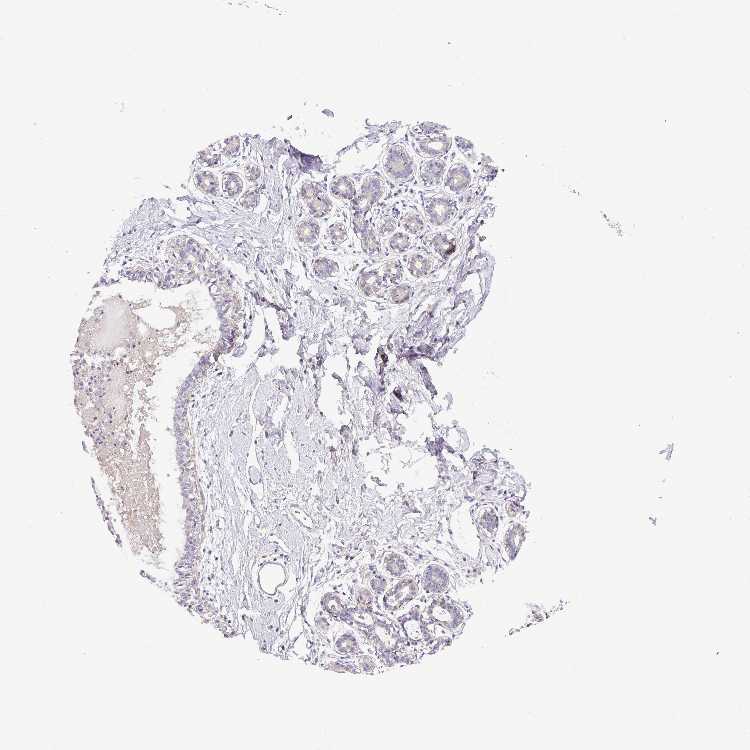

Antibody staining in the annotated cell types in the current human tissue is reported as not detected, low, medium, or high. This score is based on the staining intensity and fraction of stained cells.

Information about each individual sample is listed below, including gender, age, a tissue section image and estimated fractions of cell types. pTPM (transcripts per million) values give a quantification of the gene abundance which is comparable between different genes and samples.